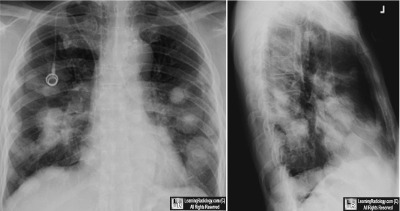

• 63 year-old male with metastatic disease to the lungs. What is the most likely primary?

Frontal and lateral radiograph of chest

4. Carcinoma of the Esophagus

Cavitary Metastases from Esophageal Carcinoma

• Metastases to the lung occur in about 30% of all malignant disease

• Routes of spread include hematogenous, lymphangitic and direct extension

• Most metastatic lung nodules develop through hematogenous spread

• Primary lung carcinomas cavitate more frequently than metastatic lesions to the lung

• Most cavitary metastases are epithelial in origin